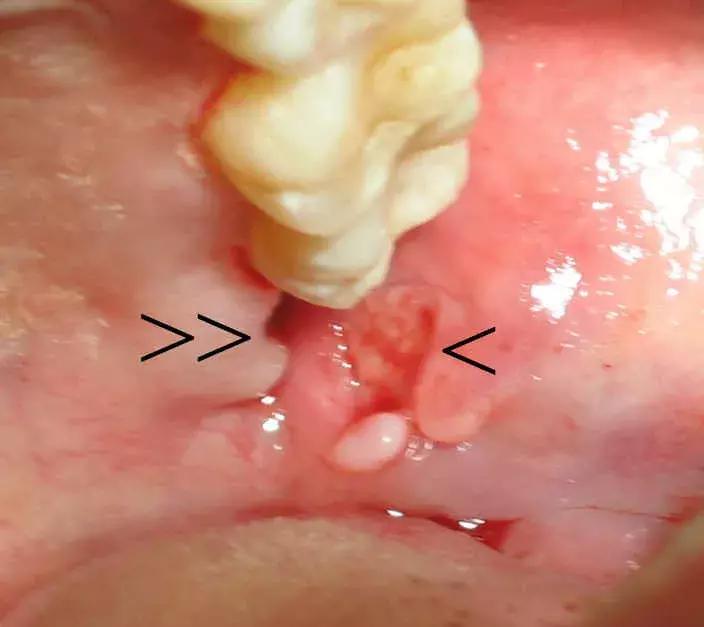

智齿阻生,萌出不全

会引起局部肿胀疼痛

不是持续的胀痛,是那种反反复复红肿,特别磨人↓

你想着,等完全长出来就去拔,这一等又是一年多。

真相是,它真的就到这为止了,就露个尖儿↓